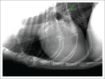

This case report shows that Mycobacterium avium subsp. paratuberculosis (MAP) infection can cause clinical disease in domestic dogs, and should be considered as a differential diagnosis for gastrointestinal inflammatory conditions. A male dachshund presented with lethargy and pain. Enlarged mesenteric lymph nodes were found on abdominal ultrasound examination. Cytological examination of lymph node aspirates was consistent with granulomatous inflammation, which was culture-confirmed as MAP. Although we were unable to confirm the source of infection, the dog's history included exposure to sheep in the Western Cape.